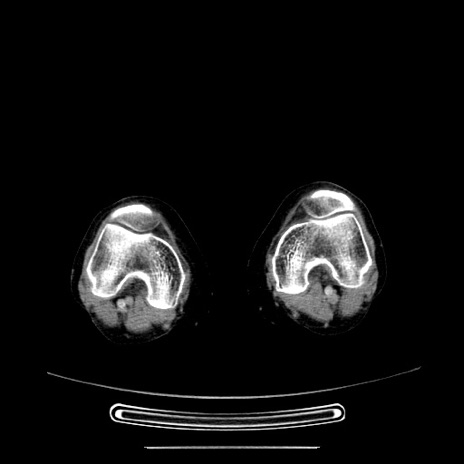

症例5(横断像)

【症例】70歳代女性

【主訴】お腹が張る

【現病歴】1週間くらい前から腹部膨満の自覚あり。昨日夜から増悪したため、本日救急外来受診。

【身体所見】意識清明、BT 36.5℃、BP 165/106mmHg、HR 80bpm、SpO2 98%、腹部:膨満、軟、自発痛・圧痛なし、触診にて不快感あり、腸蠕動音:減弱

【データ】WBC 12600、CRP 1.04